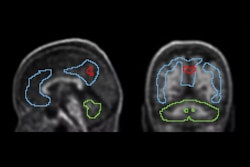

- People with a father with Alzheimer's disease had a greater spread of tau protein in the brain.

- Female study participants had a greater spread and a heavier buildup of tau protein in the brain. However, women also showed more brain resilience to amyloid beta, a predominant brain plaque found in people with Alzheimer's, leading the researchers to note that amyloid beta may be "a less important driver of atrophy in women."